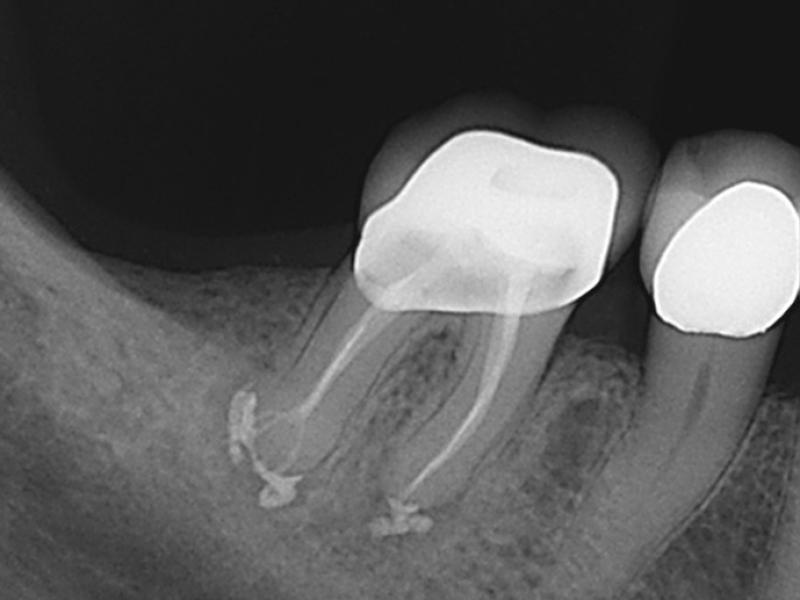

آیا عکس رادیوگرافی در بارداری خطرناک است؟

یکی از نگرانی‌های اصلی، گرفتن عکس دندان است.

واقعیت علمی:

• دوز اشعه رادیوگرافی دندان بسیار پایین است

• استفاده از پیش‌بند سربی و محافظ تیروئید خطر را تقریباً صفر می‌کند

• در موارد ضروری، رادیوگرافی با رعایت اصول ایمنی کاملاً مجاز است

عدم تشخیص دقیق بدون عکس ممکن است باعث درمان ناقص و عفونت باقی‌مانده شود.